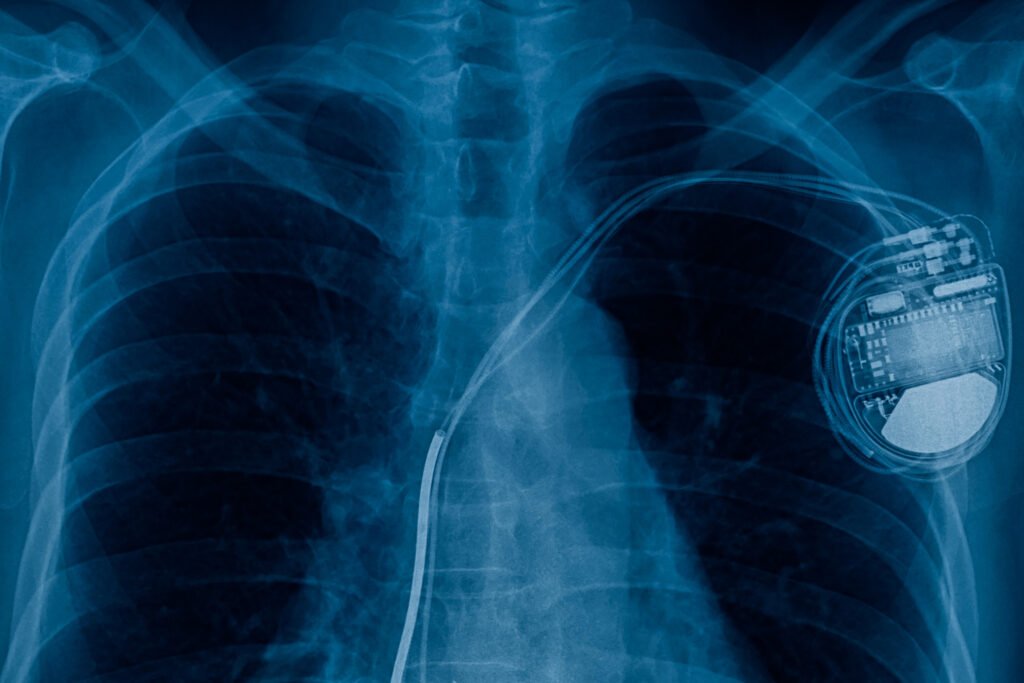

Implantable

Our simulation tools model the reception of RF energy and/or communications within the body, with respect to efficacy and safety.